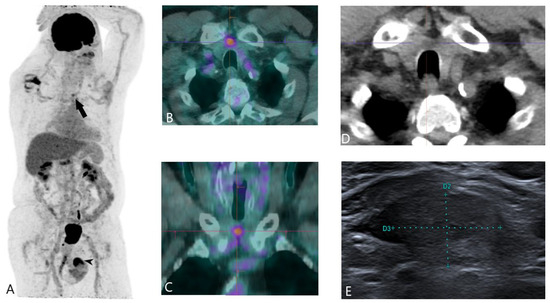

Thyroid Cancer Explore vol.3 no.2(2201 「Thyroid Cancer Expl Thyroid Cancer Treatment (PDQ®) - NCIの詳細情報

Thyroid Cancer Treatment (PDQ®) - NCI。Comparative Analysis of Metastatic Thyroid Carcinoma versus。The Role of Positron Emission Tomography/Computed Tomography。

Thyroid Cancer - Endotext - NCBI Bookshelf

Thyroid Cancer - Endotext - NCBI Bookshelf